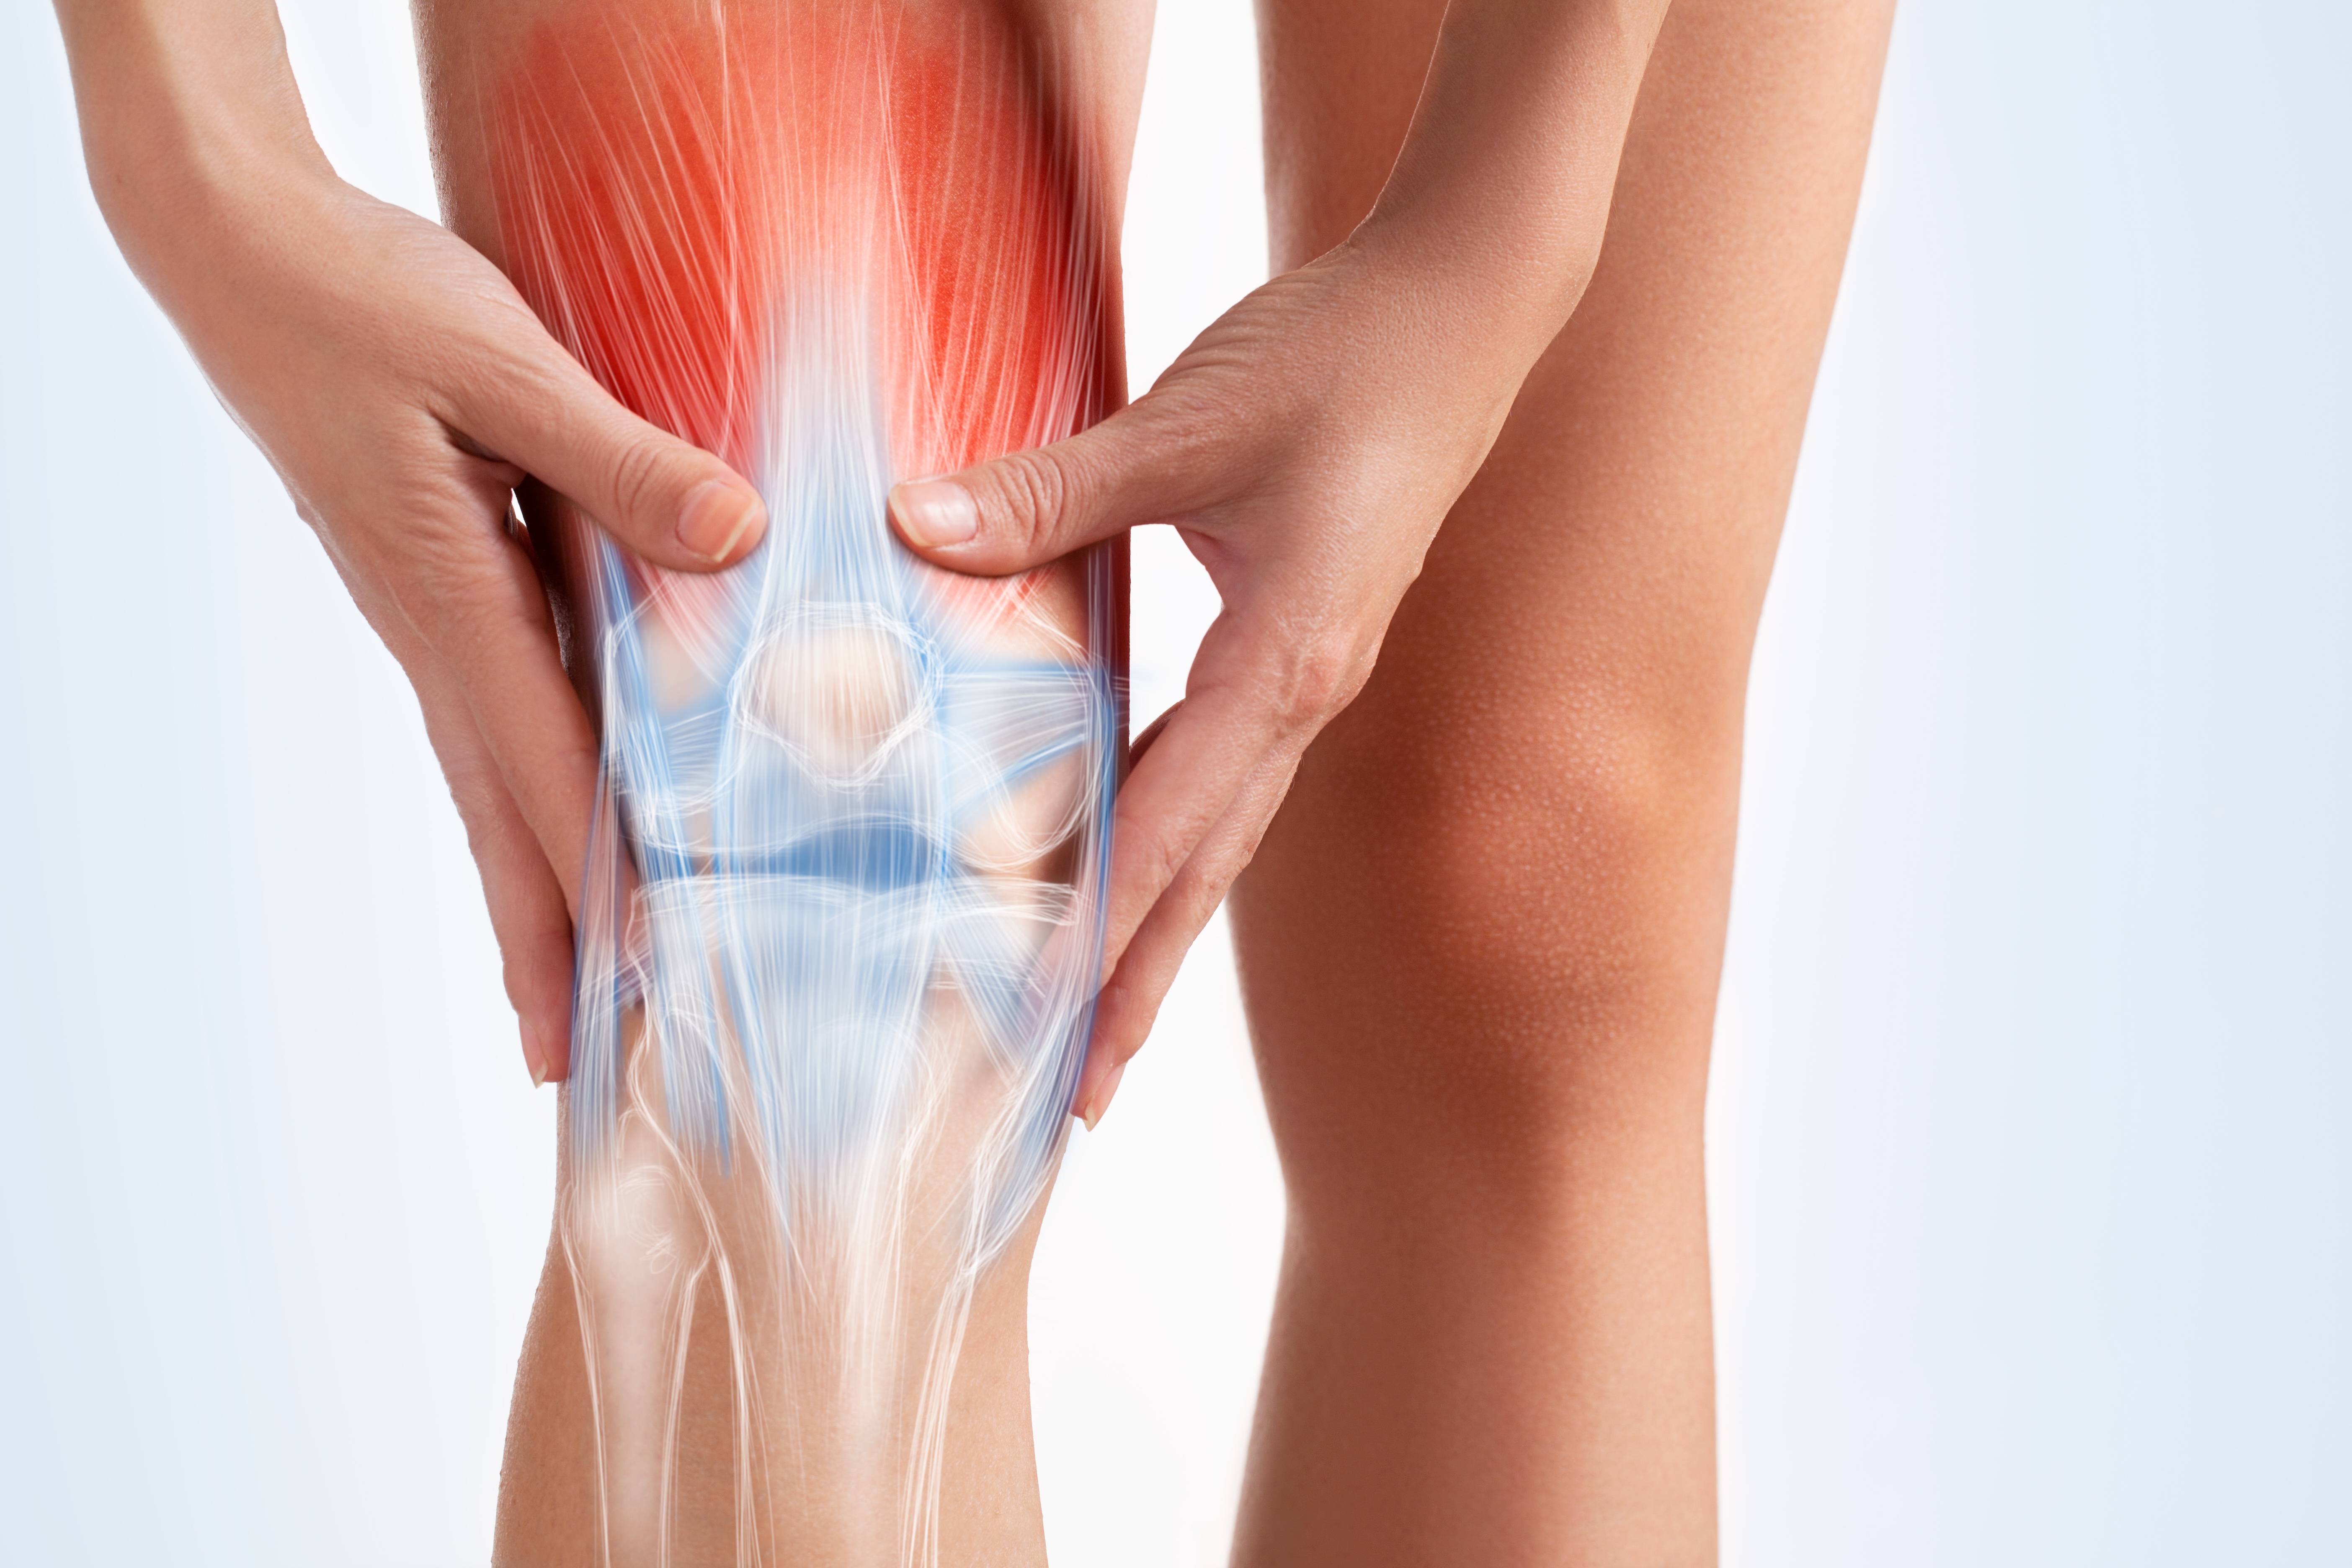

Knee joint is the largest and one of the most important joints of our body that provides stable support to the body. It allows bending and straightening of leg while walking, sitting, playing or dancing etc. It is made up of bone, cartilage, ligaments, muscles, tendons and fluid. Knee problem may occur due to damage or injury to any of these structures...